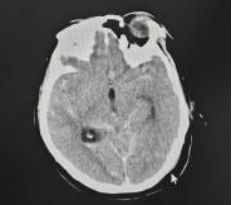

术后头颅CT

术后DSA提示动脉瘤完全夹闭

术后第二天,患者完全清醒,言语流利,问答切题,四肢活动良好,手术圆满成功。术后复查脑血管造影提示:动脉瘤夹闭完全,载瘤动脉通畅,侧支血管保护完好。